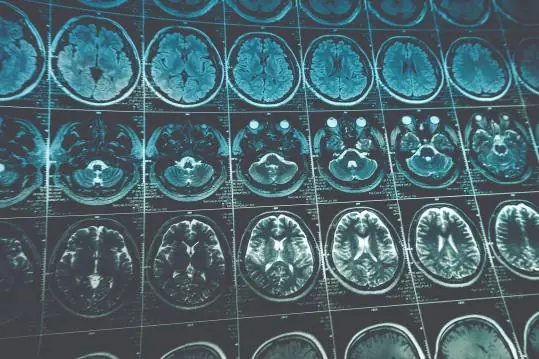

In recent years, Dr. Cavenee’s research efforts, with support from NFCR, have concentrated on glioblastoma multiforme (GBM), the most aggressive and deadliest brain tumor. His research team uncovered an abnormal version of the Epidermal Growth Factor Receptor (EGFR) – named EGFRviii – that is only present in the most rapidly-progressing tumors. With this knowledge, Dr. Cavenee’s team is now developing monoclonal antibodies, small molecules and nucleic acid-based therapeutics – known as EGFRvIII inhibitors – to target this tumor-specific molecule.